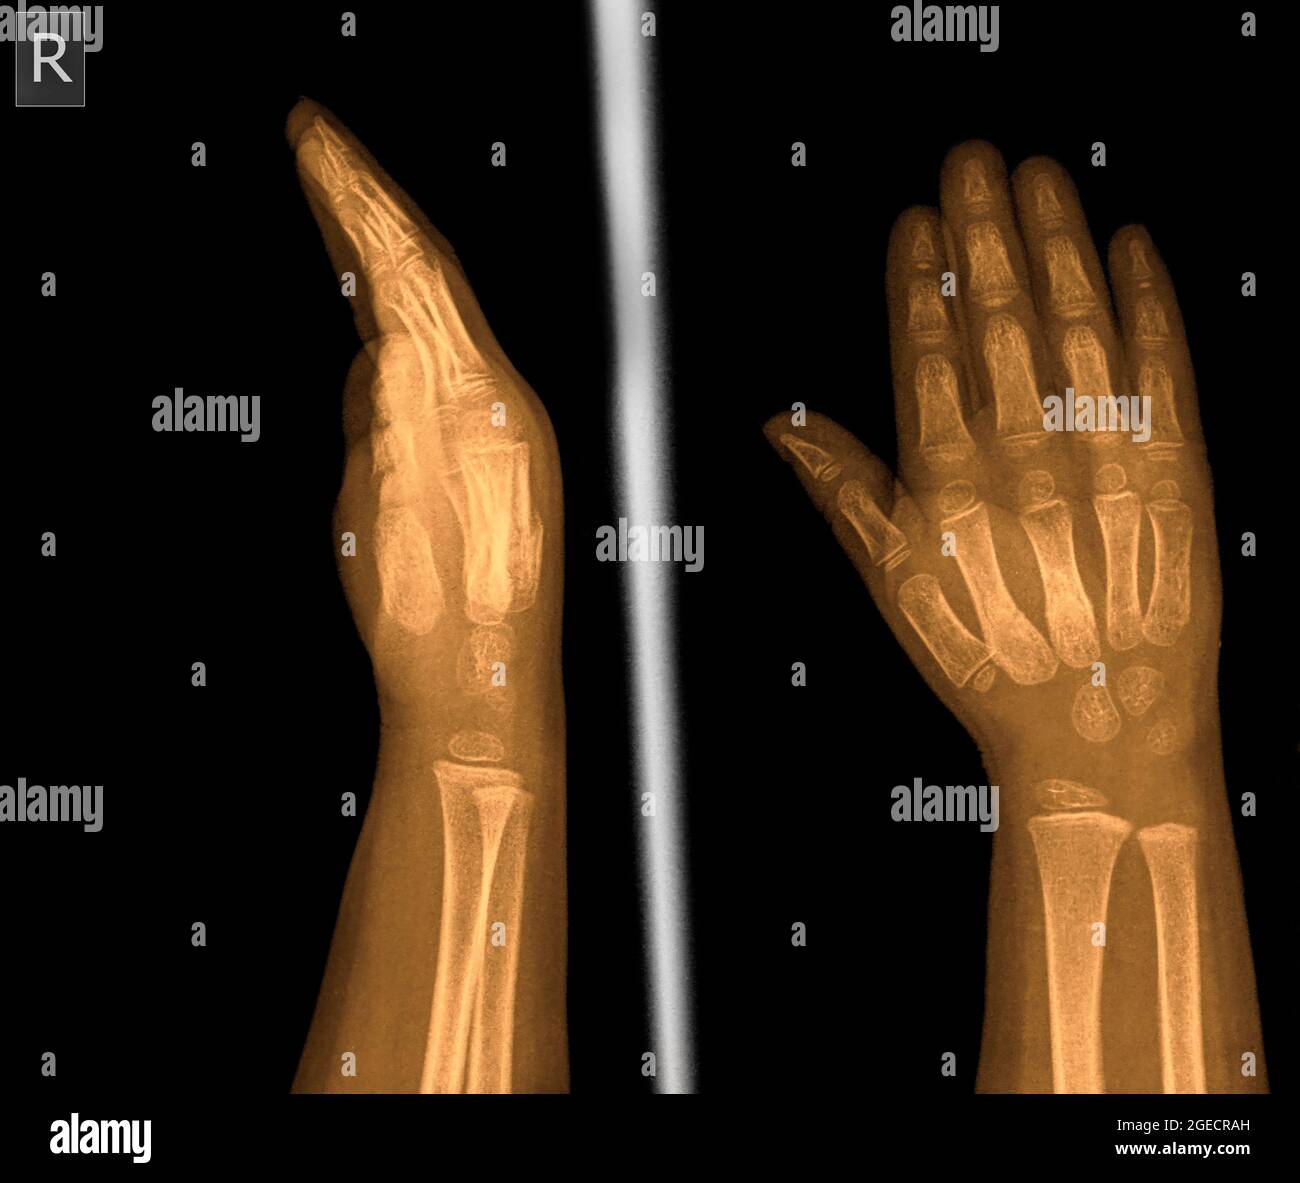

x ray of right hand and wrist

Posts: x ray of right hand and wrist